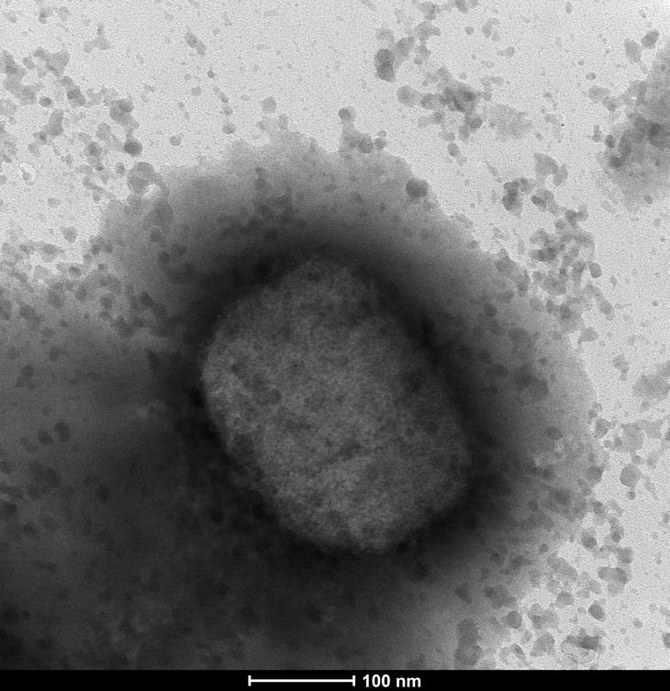

Monkeypox is a usually mild viral infection that is endemic in parts of west and central Africa.

It spreads chiefly through close contact and until the recent outbreak, was rarely seen in other parts of the world, which is why the recent emergence of cases in Europe, the United States and other areas has raised alarms.